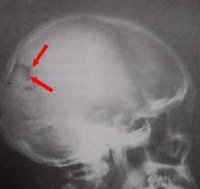

2、颅的侧面观颅的侧面在乳突的前上方可见外耳门,向内通外耳道。外耳门前上方的弓形骨梁称颧弓。颧弓的内上方有一浅而大的窝,称颞窝。在颞窝,额、顶、颞、蝶四骨会合处,常构成“H”形的缝,称为翼点。此处骨质较薄,内有脑膜中动脉前支通过,若发生骨折时,容易损伤该动脉,引起颅内血肿。颞窝下方的窝称颞下窝,颞下窝向内通翼腭窝。翼腭窝向下、向内侧、向前、向后及向外分别与口腔、鼻腔、眶、颅腔及颞下窝相交通,是许多血管神经的通道。